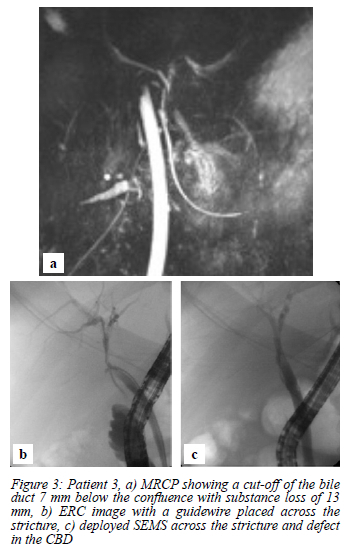

A 47-year-old female was referred from a neighbouring country. She represented five days after a LC with pain and peritonitis at the referring hospital, where a laparotomy and washout were performed and a 6F feeding tube was placed through an opening in the bile duct into the CHD. An MRCP was done two weeks after the initial injury which showed a cut-off of the bile duct 7 mm below the confluence with substance loss of 13 mm (Figure 3a) (MBD2 Dc LS 13 VBI- L Me). She was referred to our unit eight weeks after the LC for a bile duct repair. A cholangiogram via the percutaneous drain showed a stricture below the confluence, with distal CBD continuity (MBD2 Dp LS 13 VBI- L Me). At ERC a SEMS was deployed through the stricture covering the defect in the CBD (Figure 3b, 3c). The patient was discharged with normal bilirubin levels, with stent exchanges planned every three months for a total stent period of one year.